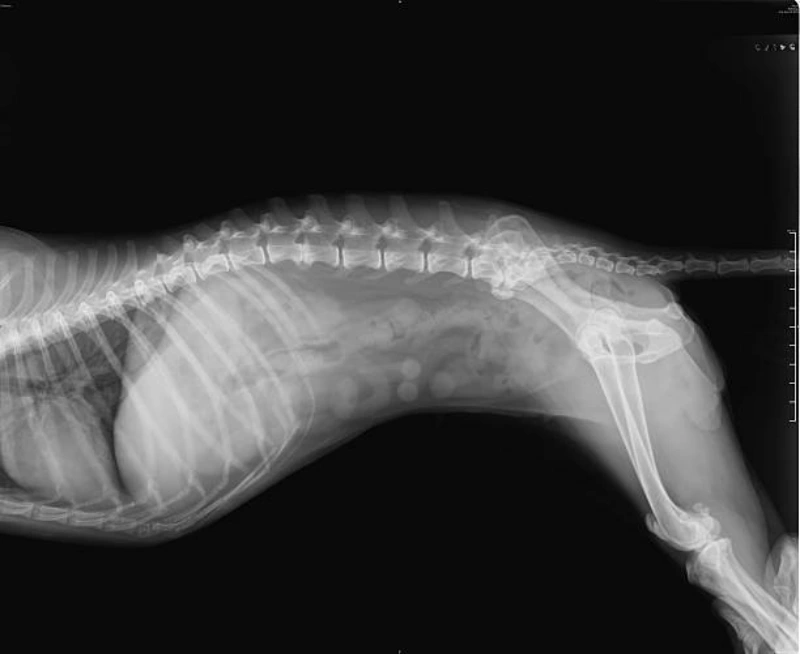

O raio x veterinário é um exame de imagem amplamente utilizado na medicina animal para identificar alterações ósseas e internas.

Ele auxilia no diagnóstico de fraturas, luxações, problemas respiratórios e até complicações abdominais.

O raio x veterinário é uma técnica de imagem que utiliza radiação para produzir imagens dos tecidos internos dos animais.

Essas imagens são essenciais para identificar possíveis lesões, fraturas, tumores e outras condições que não são visíveis a olho nu.

Através do raio X, os veterinários conseguem realizar diagnósticos precisos e planejar o tratamento mais adequado para cada caso, assegurando o bem-estar dos animais.